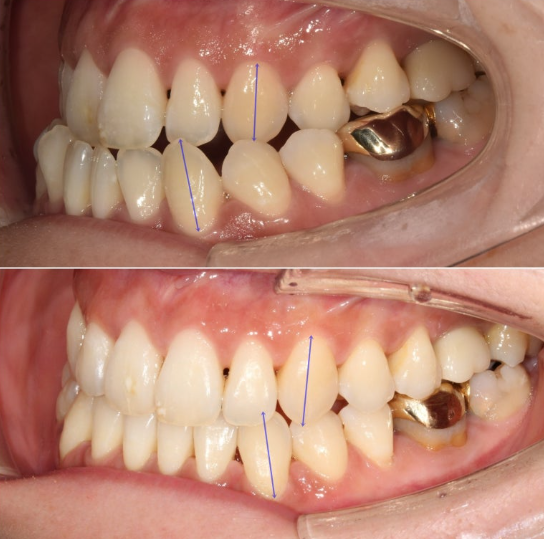

24.01~25.07

앞니뿐만 아니라 큰어금니까지 반대교합입니다.

앞니 중심선은 약 2mm 어긋나 있습니다.

어금니 역시 심한 3급 교합관계를 보입니다. 앞니는 반대교합으로 거꾸로 물립니다.